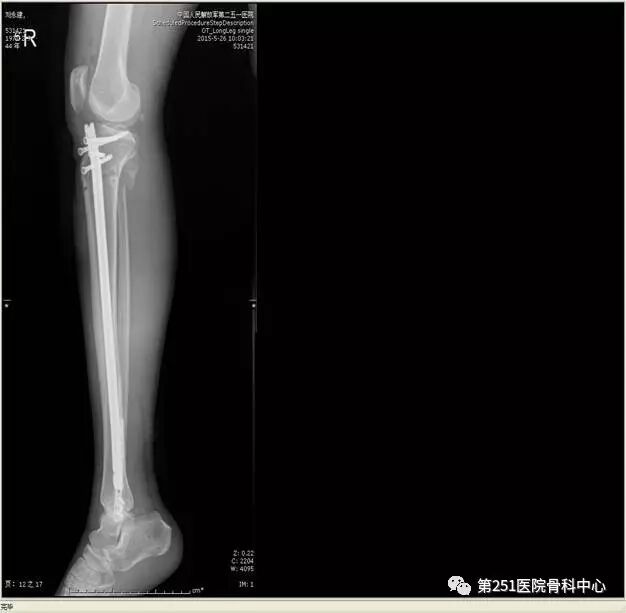

病例6:男性,39岁,车祸伤SchatzkerⅥ型胫骨平台骨折。

![]()